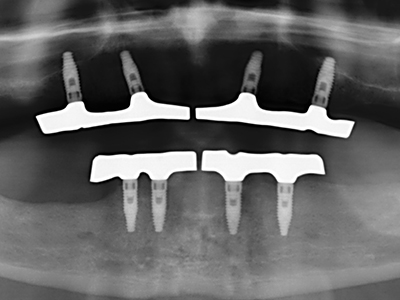

Fig. 13: Adequate irrigation with the 4-mm residual bone width is essential for this 52-year-old patient during the bone splitting.

Fig. 14: Placement of four tapered RSX implants (Bego Implant Systems, Bremen).

Fig. 15: The one-year follow-up x-ray examination shows stable conditions at the bone level.

Fig. 16: The intraoral conditions are also stable with embedding of the implants in keratinized gingiva.